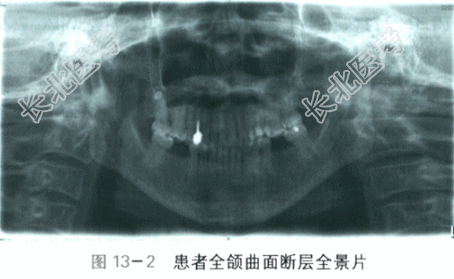

全颌曲面断层片显示:髁状突、喙突、下颌骨升支、体部、上颌窦等解剖结构未见异常,18牙发育不良埋伏阻生,28、38、48、36、46缺失,14为高密度桩核影像,37牙牙冠

面见高密度充填物影像,全口牙槽嵴顶显影清晰、高度未见降低,骨小梁密度纹理无异常(见图13-2)。